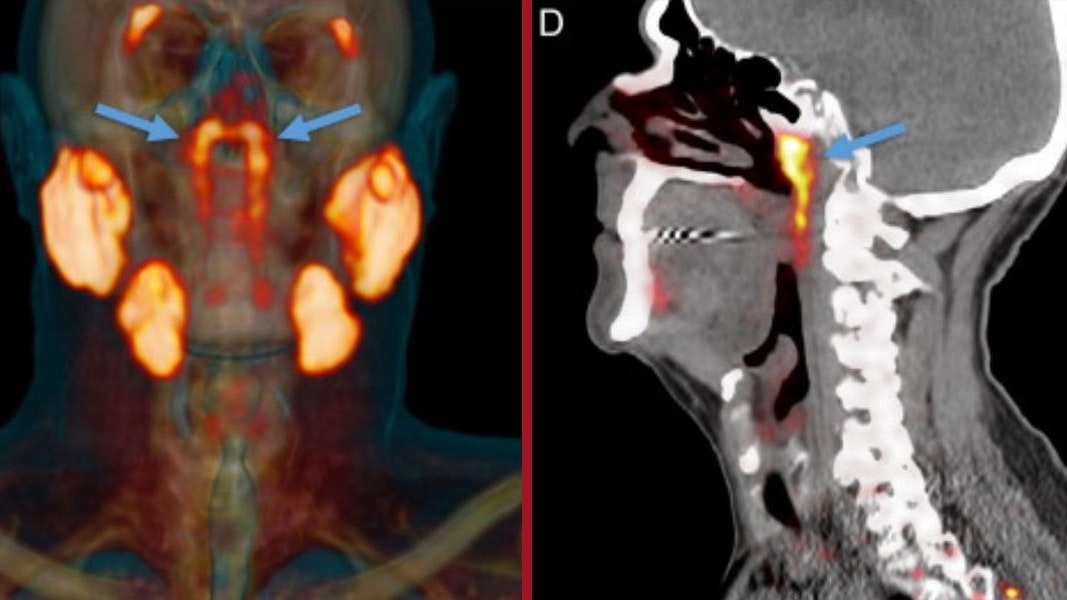

Die Tubariusdrüse (blaue Pfeile) befindet sich im Nasenrachenraum.